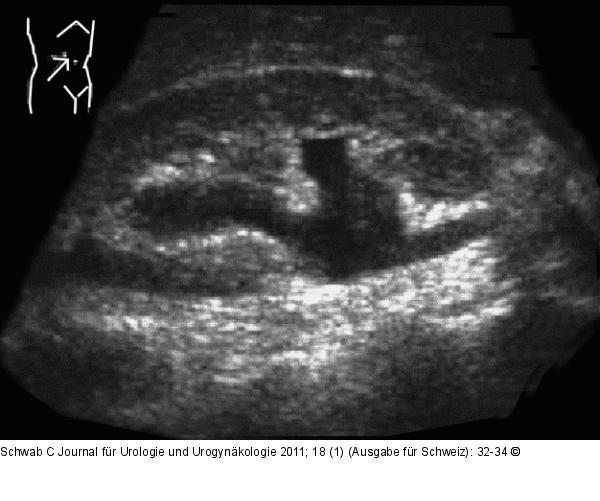

Abbildung 2: Nierendilatation Nierendilatation in der Sonographie |